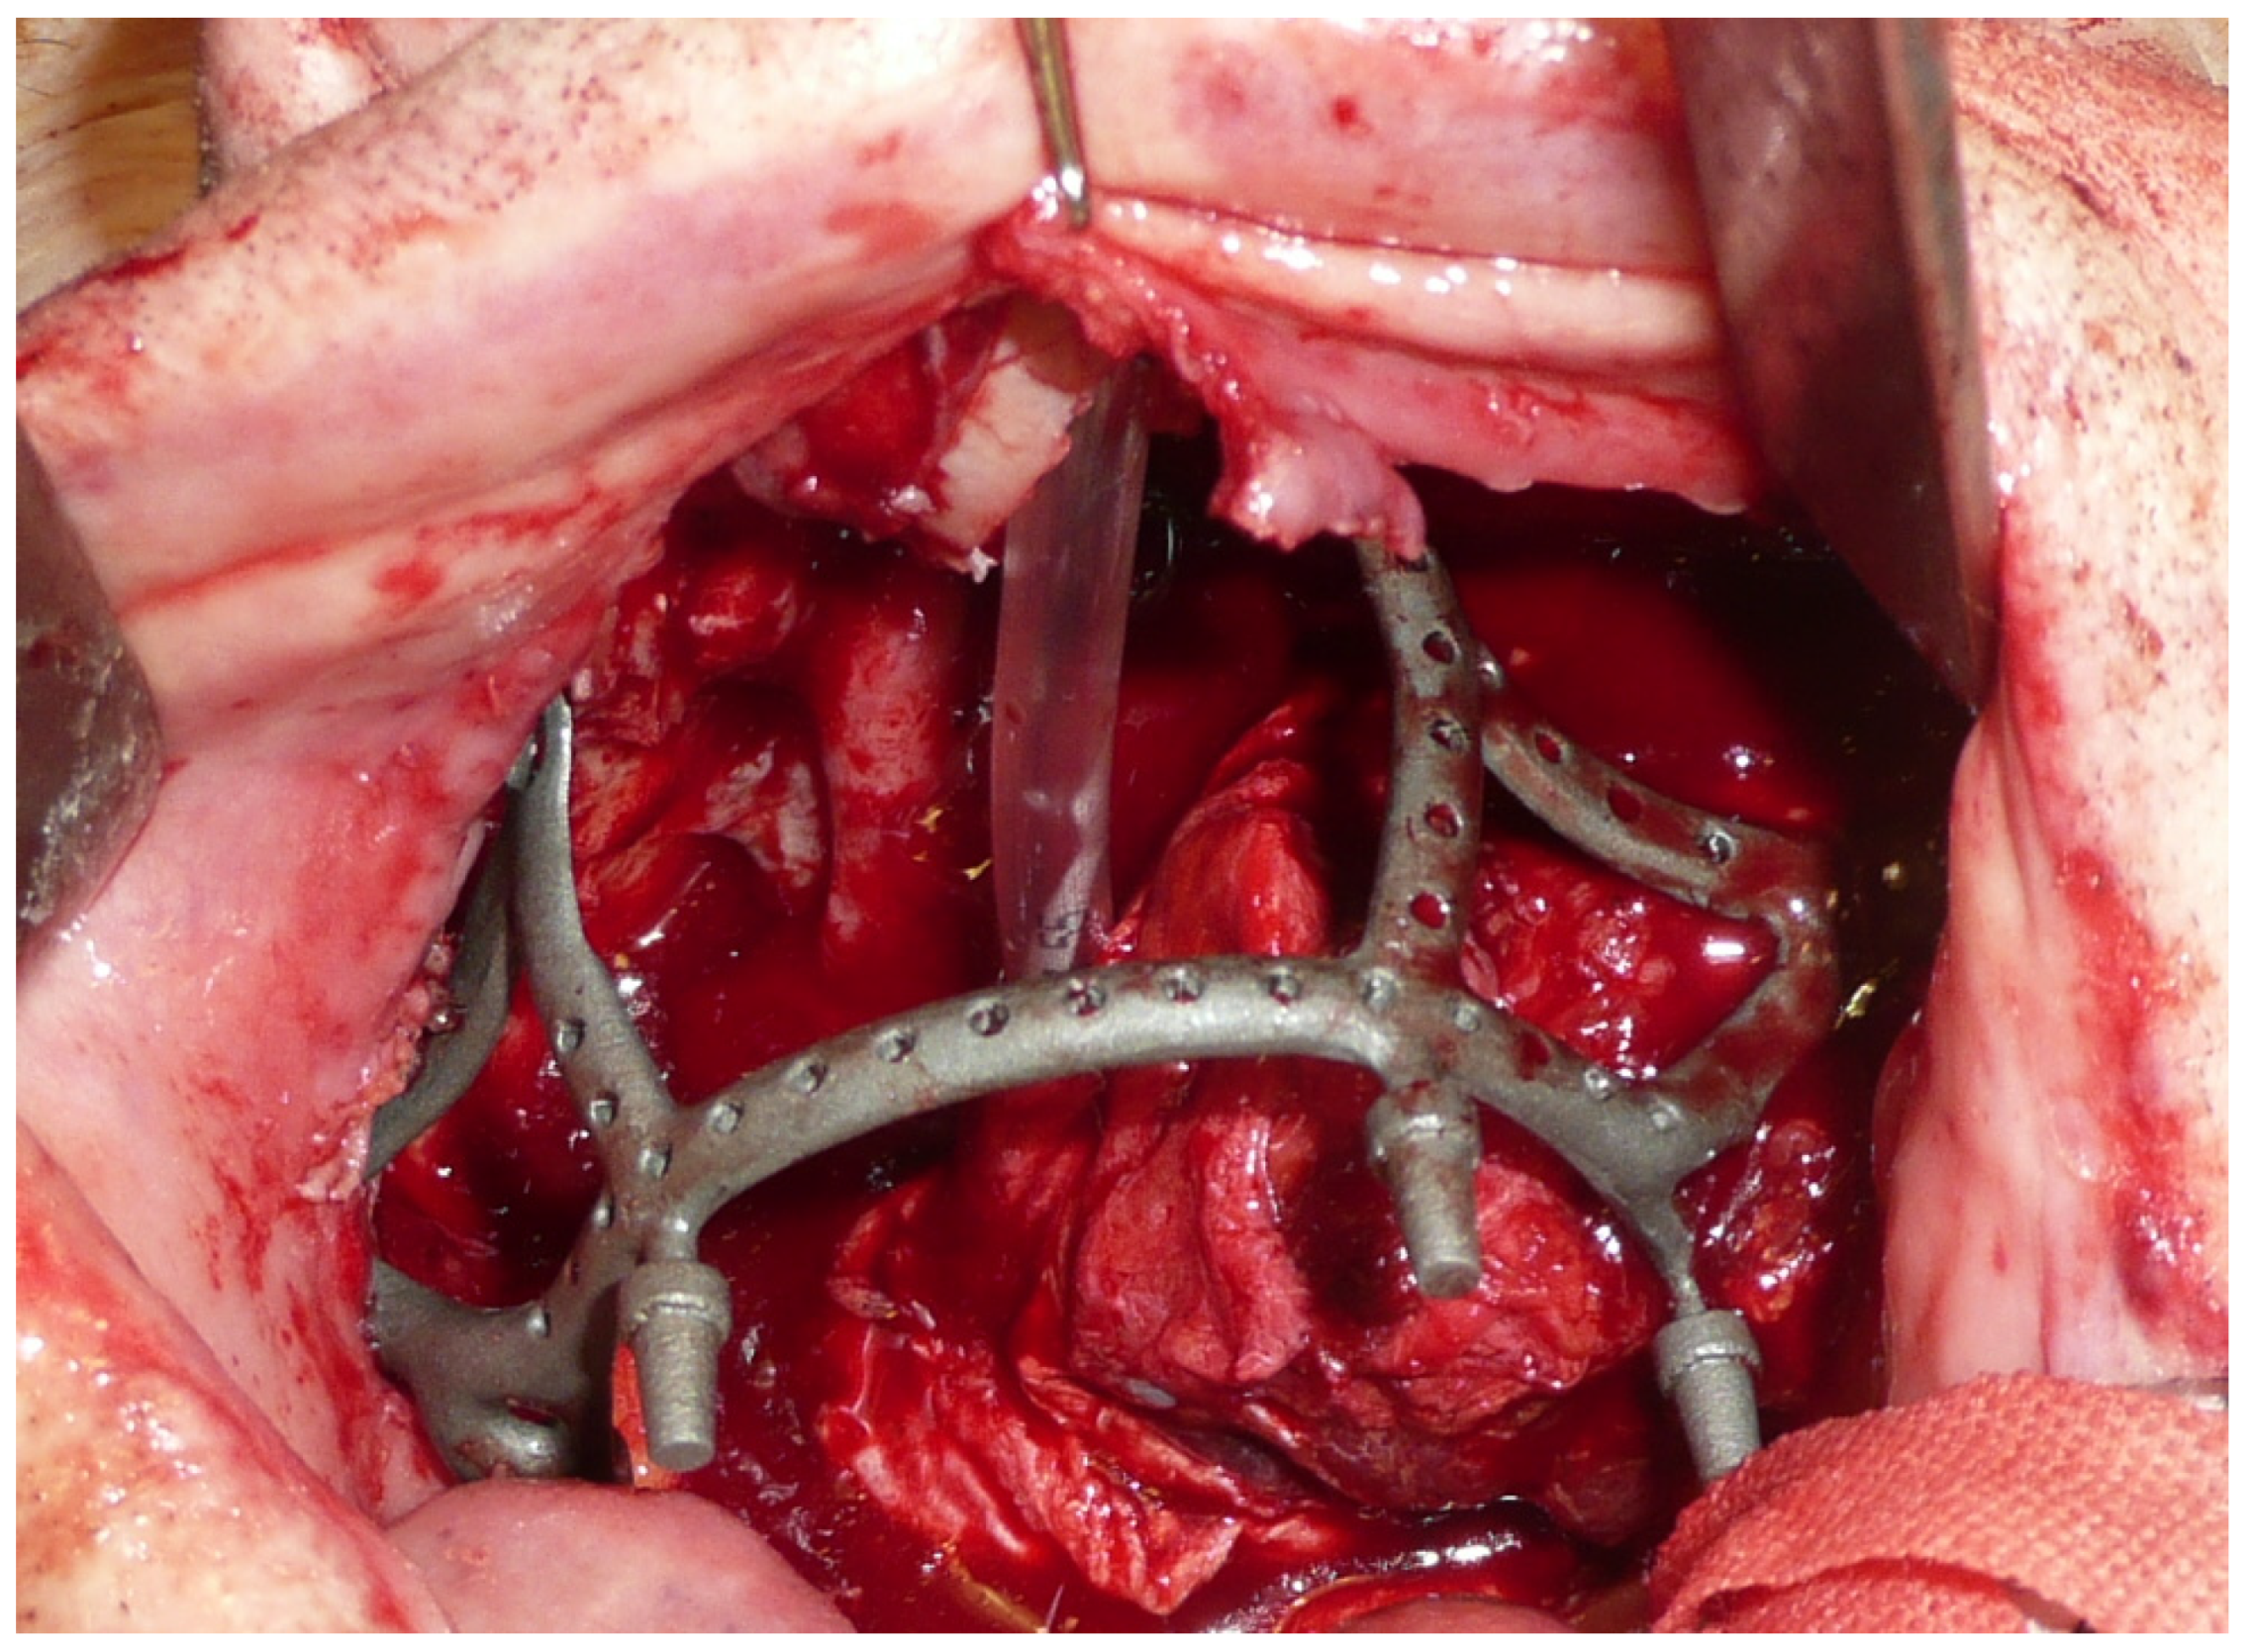

The surgery was performed under general anesthesia with orotracheal intubation. Through a circumvestibular mucosal incision with releases on the tuber maxillae bilaterally, the maxilla was completely skeletonized up to the zygomatic knobs laterally and the apical portion of the nasomaxillary pillars medially. The cutting guides were then positioned, and the bone osteotomy was performed. After detaching the pterygoid plates, the maxilla was mobilized, and the resection was completed by incising the mucosa at the boundary between the hard and soft palate. The subperiosteal implant was then placed and fixed with 2.0 osteosynthesis screws (Stryker, Kalamazoo, MI, USA) on the nasomaxillary pillars and zygomatic knobs [Figure 4].

Figure 4.

Intraoperative view of the implant placed in the recipient site.